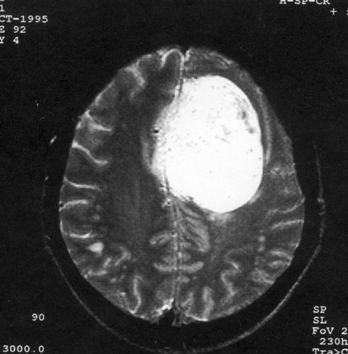

问题 病历摘要:??患者,男,40岁。发作性左下肢抽搐1年余,每次发作3~5分,每周发作1~2次。每次发作后感左下肢乏力,约半日后可自行恢复。既往身体健康。体检:神清,头顶部偏右有局限性骨性隆起(1.5×1.5cm),左鼻唇沟稍浅,伸舌居中。感觉、运动无明显异常。左浅反射减退,左下肢腱反射稍亢进,左Babinski征(-)。 可选择下列哪些检查帮助诊断